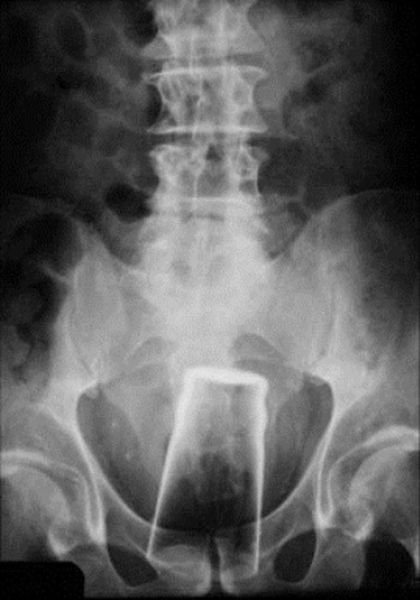

Не забываем и о классических снимках: кружка пива в заднем проходе!![]()

На этом снимке изображена часть 60-летнего мужчины, пришедшего в больницу Ништар (Nishtar Hospital) в Мултане (Multan), Пакистан. Он решил обратиться к врачам так, как воры вставили в его анус банку Пепси, после чего украли двух его буйволов.![]()

Это происшествие не было несчастным случаем, а преднамеренным действием. Погибший Райан Данн (Ryan Dunn) из телешоу «Чудаков» сознательно вставил модельку автомобиля просто, чтобы поиздеваться над врачами Скорой Помощи.![]()